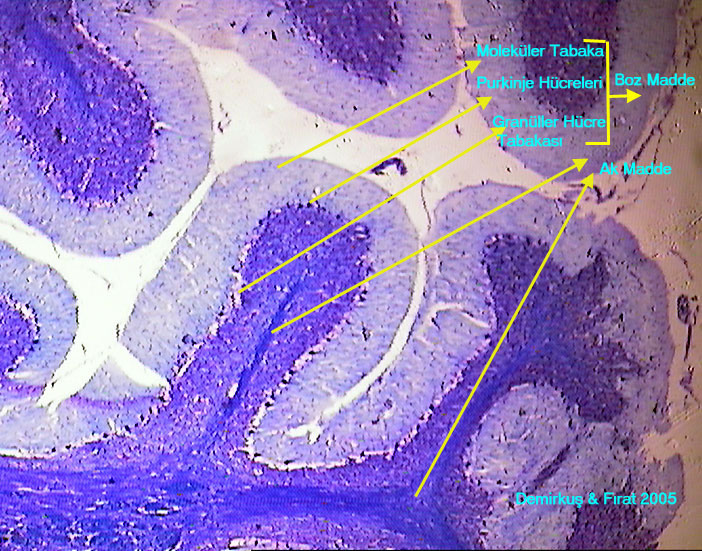

a/beyincik-------x10.jpg